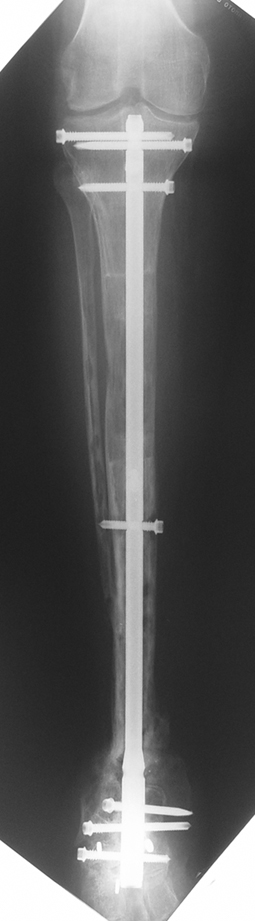

Debridement and resection of bone fragment from the pseudarhtosis area vascularized or nonvascularized fibula graft, vascularized muscle flaps, bone grafting followed internal fixation techniques make a option for treatment of pseudarthrosis treatment. But these treatment modalities may not correct deformity and leg-length discrepancy.

Case 3